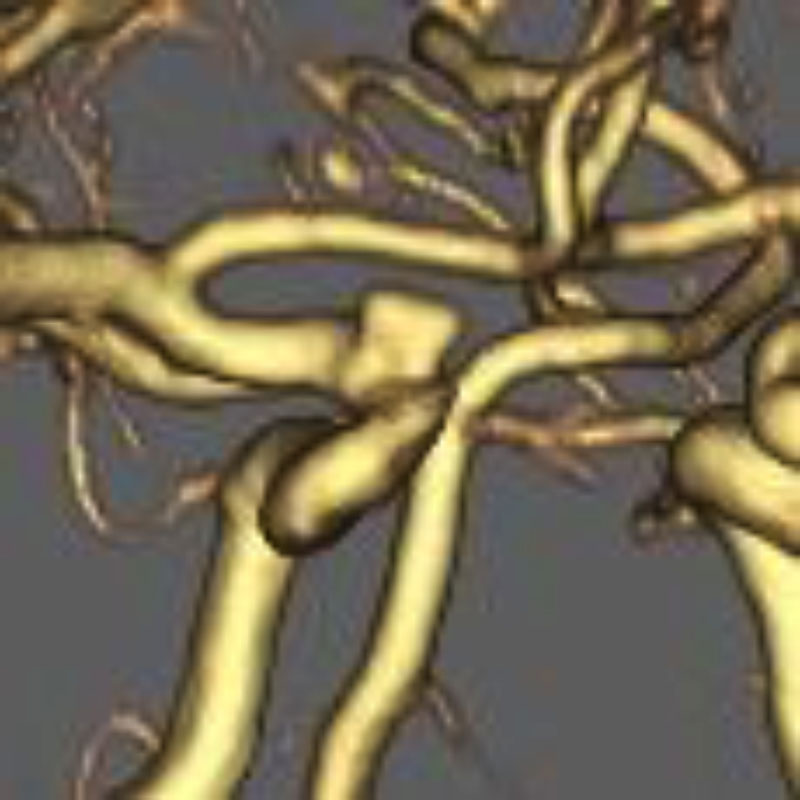

左内頚動脈狭窄症

経皮的頸動脈ステント留置術

住吉/木本